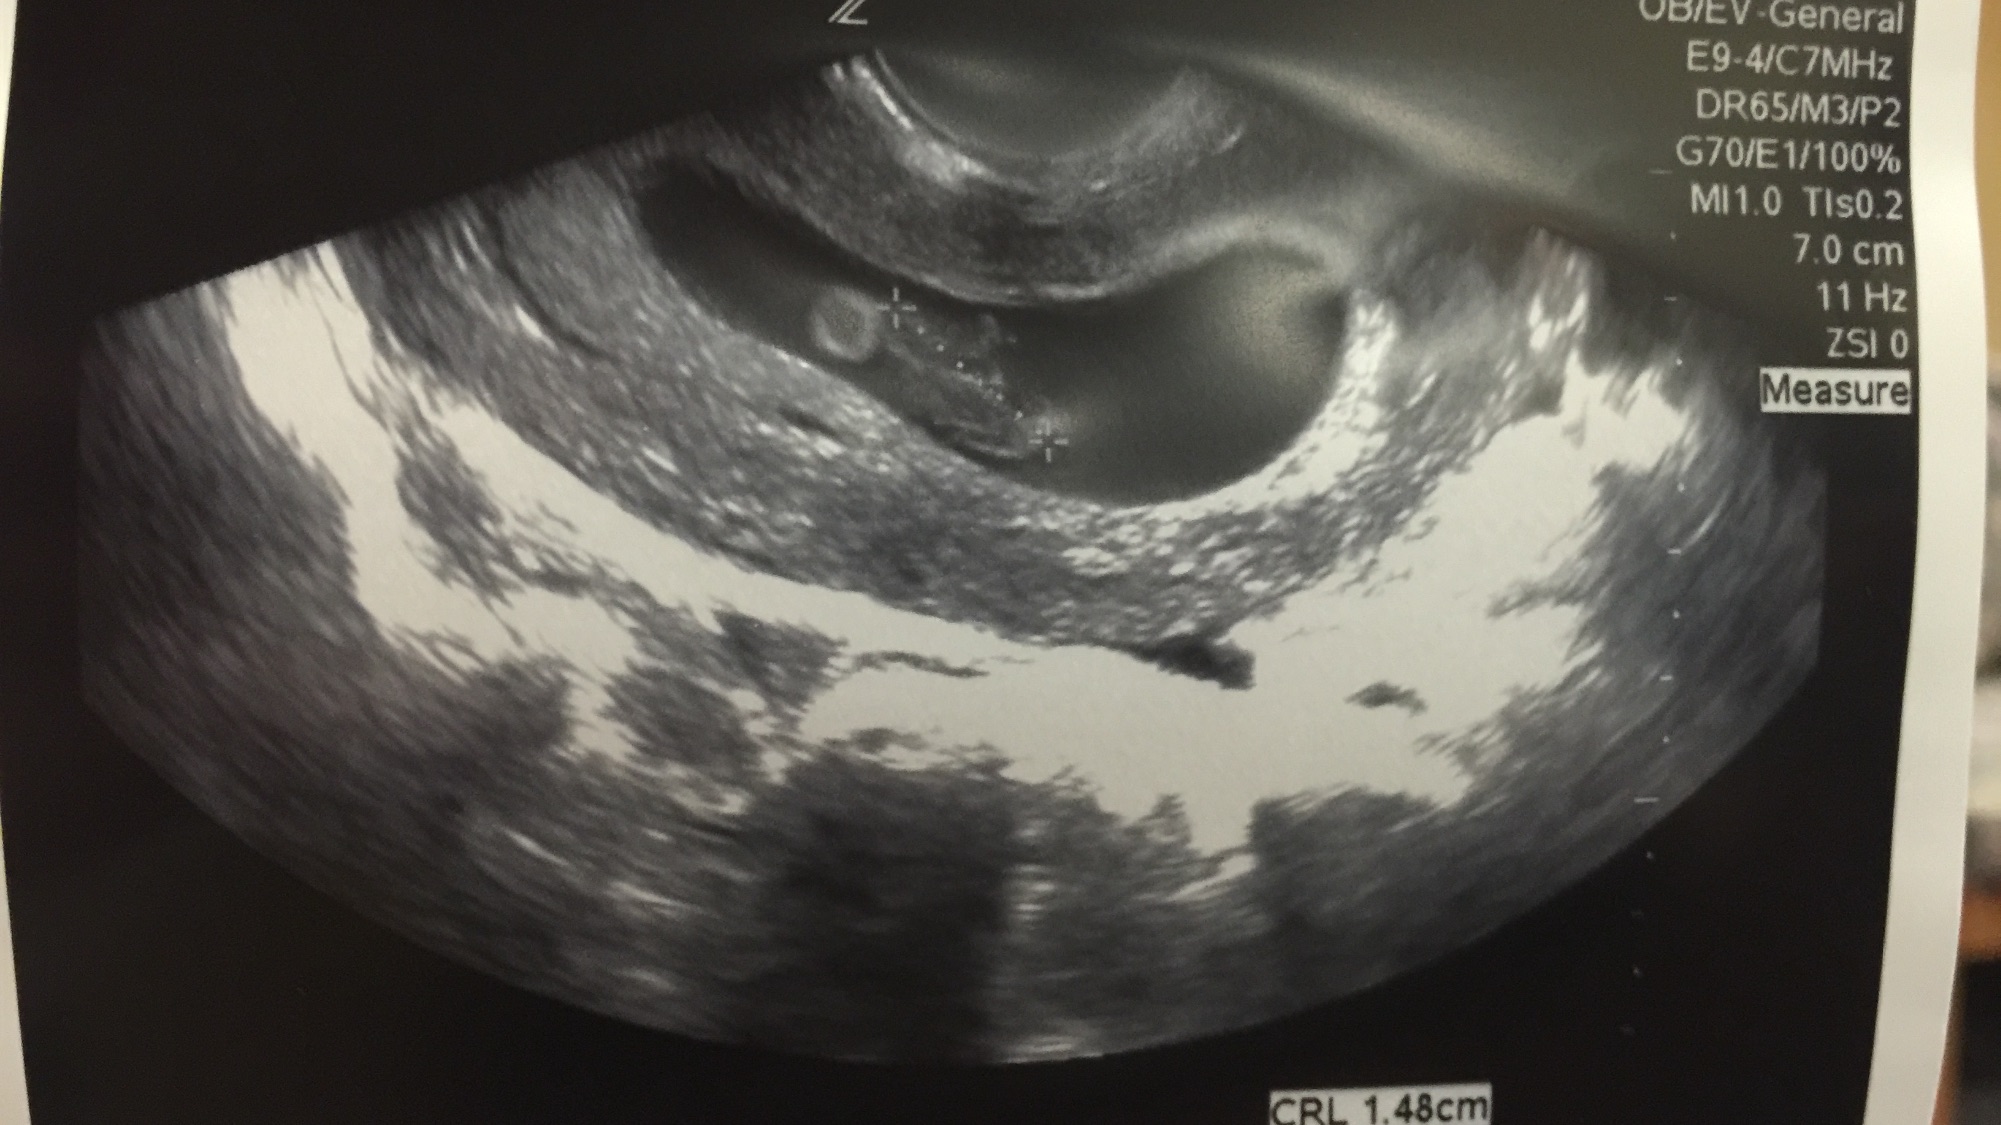

This is my first post, but I am due 2/5/16 with my first little one. Heart rate was 167, and I'm 9w2d right now. US was taken at 8w4d